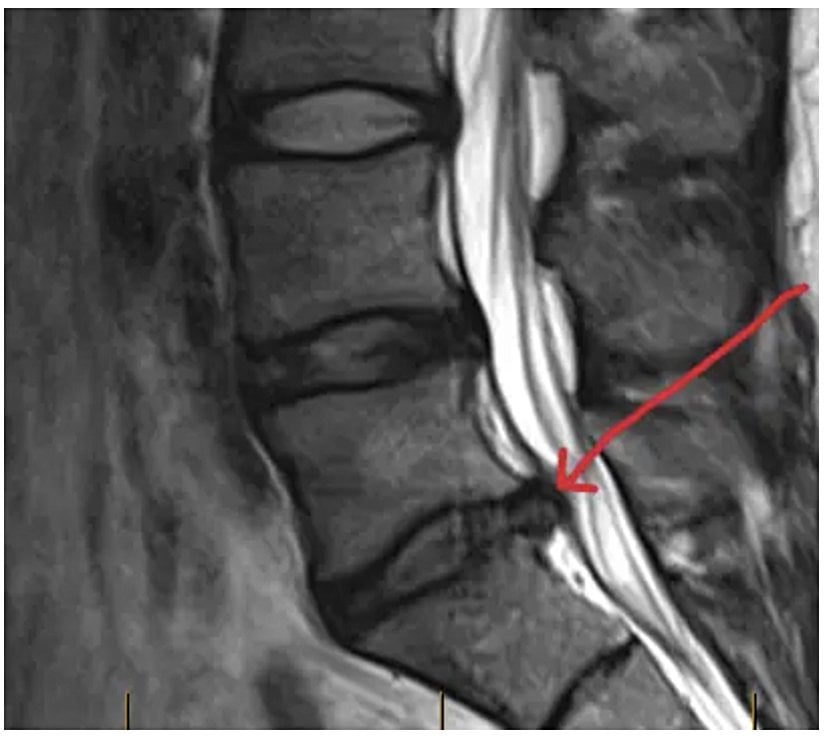

Bu büyük ve sabit manyetik alanın (B0⃗\vec{B_0}) içerisine girildiği zaman vücudumuzdaki milyarlarca hidrojen atomunun protonları, yani o küçük mıknatıslar artık rastgele yönlere bakar durumda değillerdir (Şekil 1). B0⃗\vec{B_0} alanı ile aynı (paralel) veya zıt yönde yönelmişlerdir. Paralel durumdaki protonlar paralel olmayanlara göre biraz daha düşük enerji seviyesindedir. Paralel protonların sayısı paralel olmayanlardan çok küçük oranda daha fazladır. Bu küçük fark B0⃗\vec{B_0} yönünde, ki genellikle bu vücut uzun ekseni boyunca olur, net bir manyetizasyon vektörü (M⃗\vec{M}) oluşturur. Protonlar artık dengededir ve B0⃗\vec{B_0} etrafında bir topaç gibi presesyon hareketi yapmaktadırlar (Şekil 2).[2]